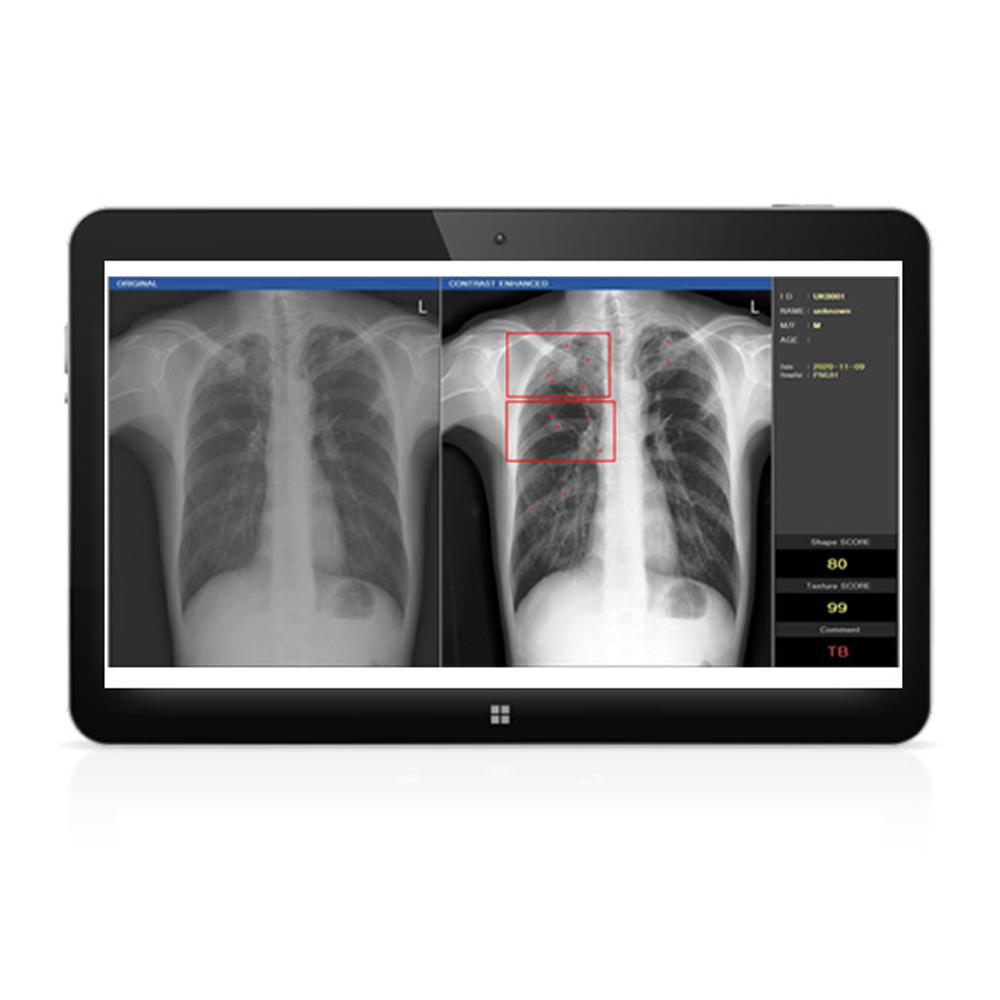

DxRAD(Digital X-ray Radiography Auto Decipher based on AI)

The DxRAD is a complementary tool that fits easily on a regular chest X-Ray scan to detect three kinds of chest diseases instantly; normal, abnormal and tuberculosis allowing patients to receive their results and start treatment immediately to avoid further transmission and infections. DxRAD running process is that after scanning chest, the first signal reaches the DxRAD and the result goes to the server of the hospital. From the transferred file, we can see the results. Also the result can be stored in the second hard disk to be used for deep learning and improve future readings..

The DxRAD is a complementary tool that fits easily on a regular chest X-Ray scan to detect three kinds of chest diseases instantly; normal, abnormal and tuberculosis allowing patients to receive their results and start treatment immediately to avoid further transmission and infections. DxRAD running process is that after scanning chest, the first signal reaches the DxRAD and the result goes to the server of the hospital. From the transferred file, we can see the results. Also the result can be stored in the second hard disk to be used for deep learning and improve future readings..

Auto decipher normal, abnormal, tuberculosis

DxRAD Development

Need for exact examination of tuberculous (Chest X-Ray)

70% of hospitals do not have any Radionic Technologist

Patients have not received exact tuberculous test through chest X-Ray

For tuberculous, the early diagnosis is key

DxRAD Development

Need for exact examination of tuberculous (Chest X-Ray)

70% of hospitals do not have any Radionic Technologist

Patients have not received exact tuberculous test through chest X-Ray

For tuberculous, the early diagnosis is key